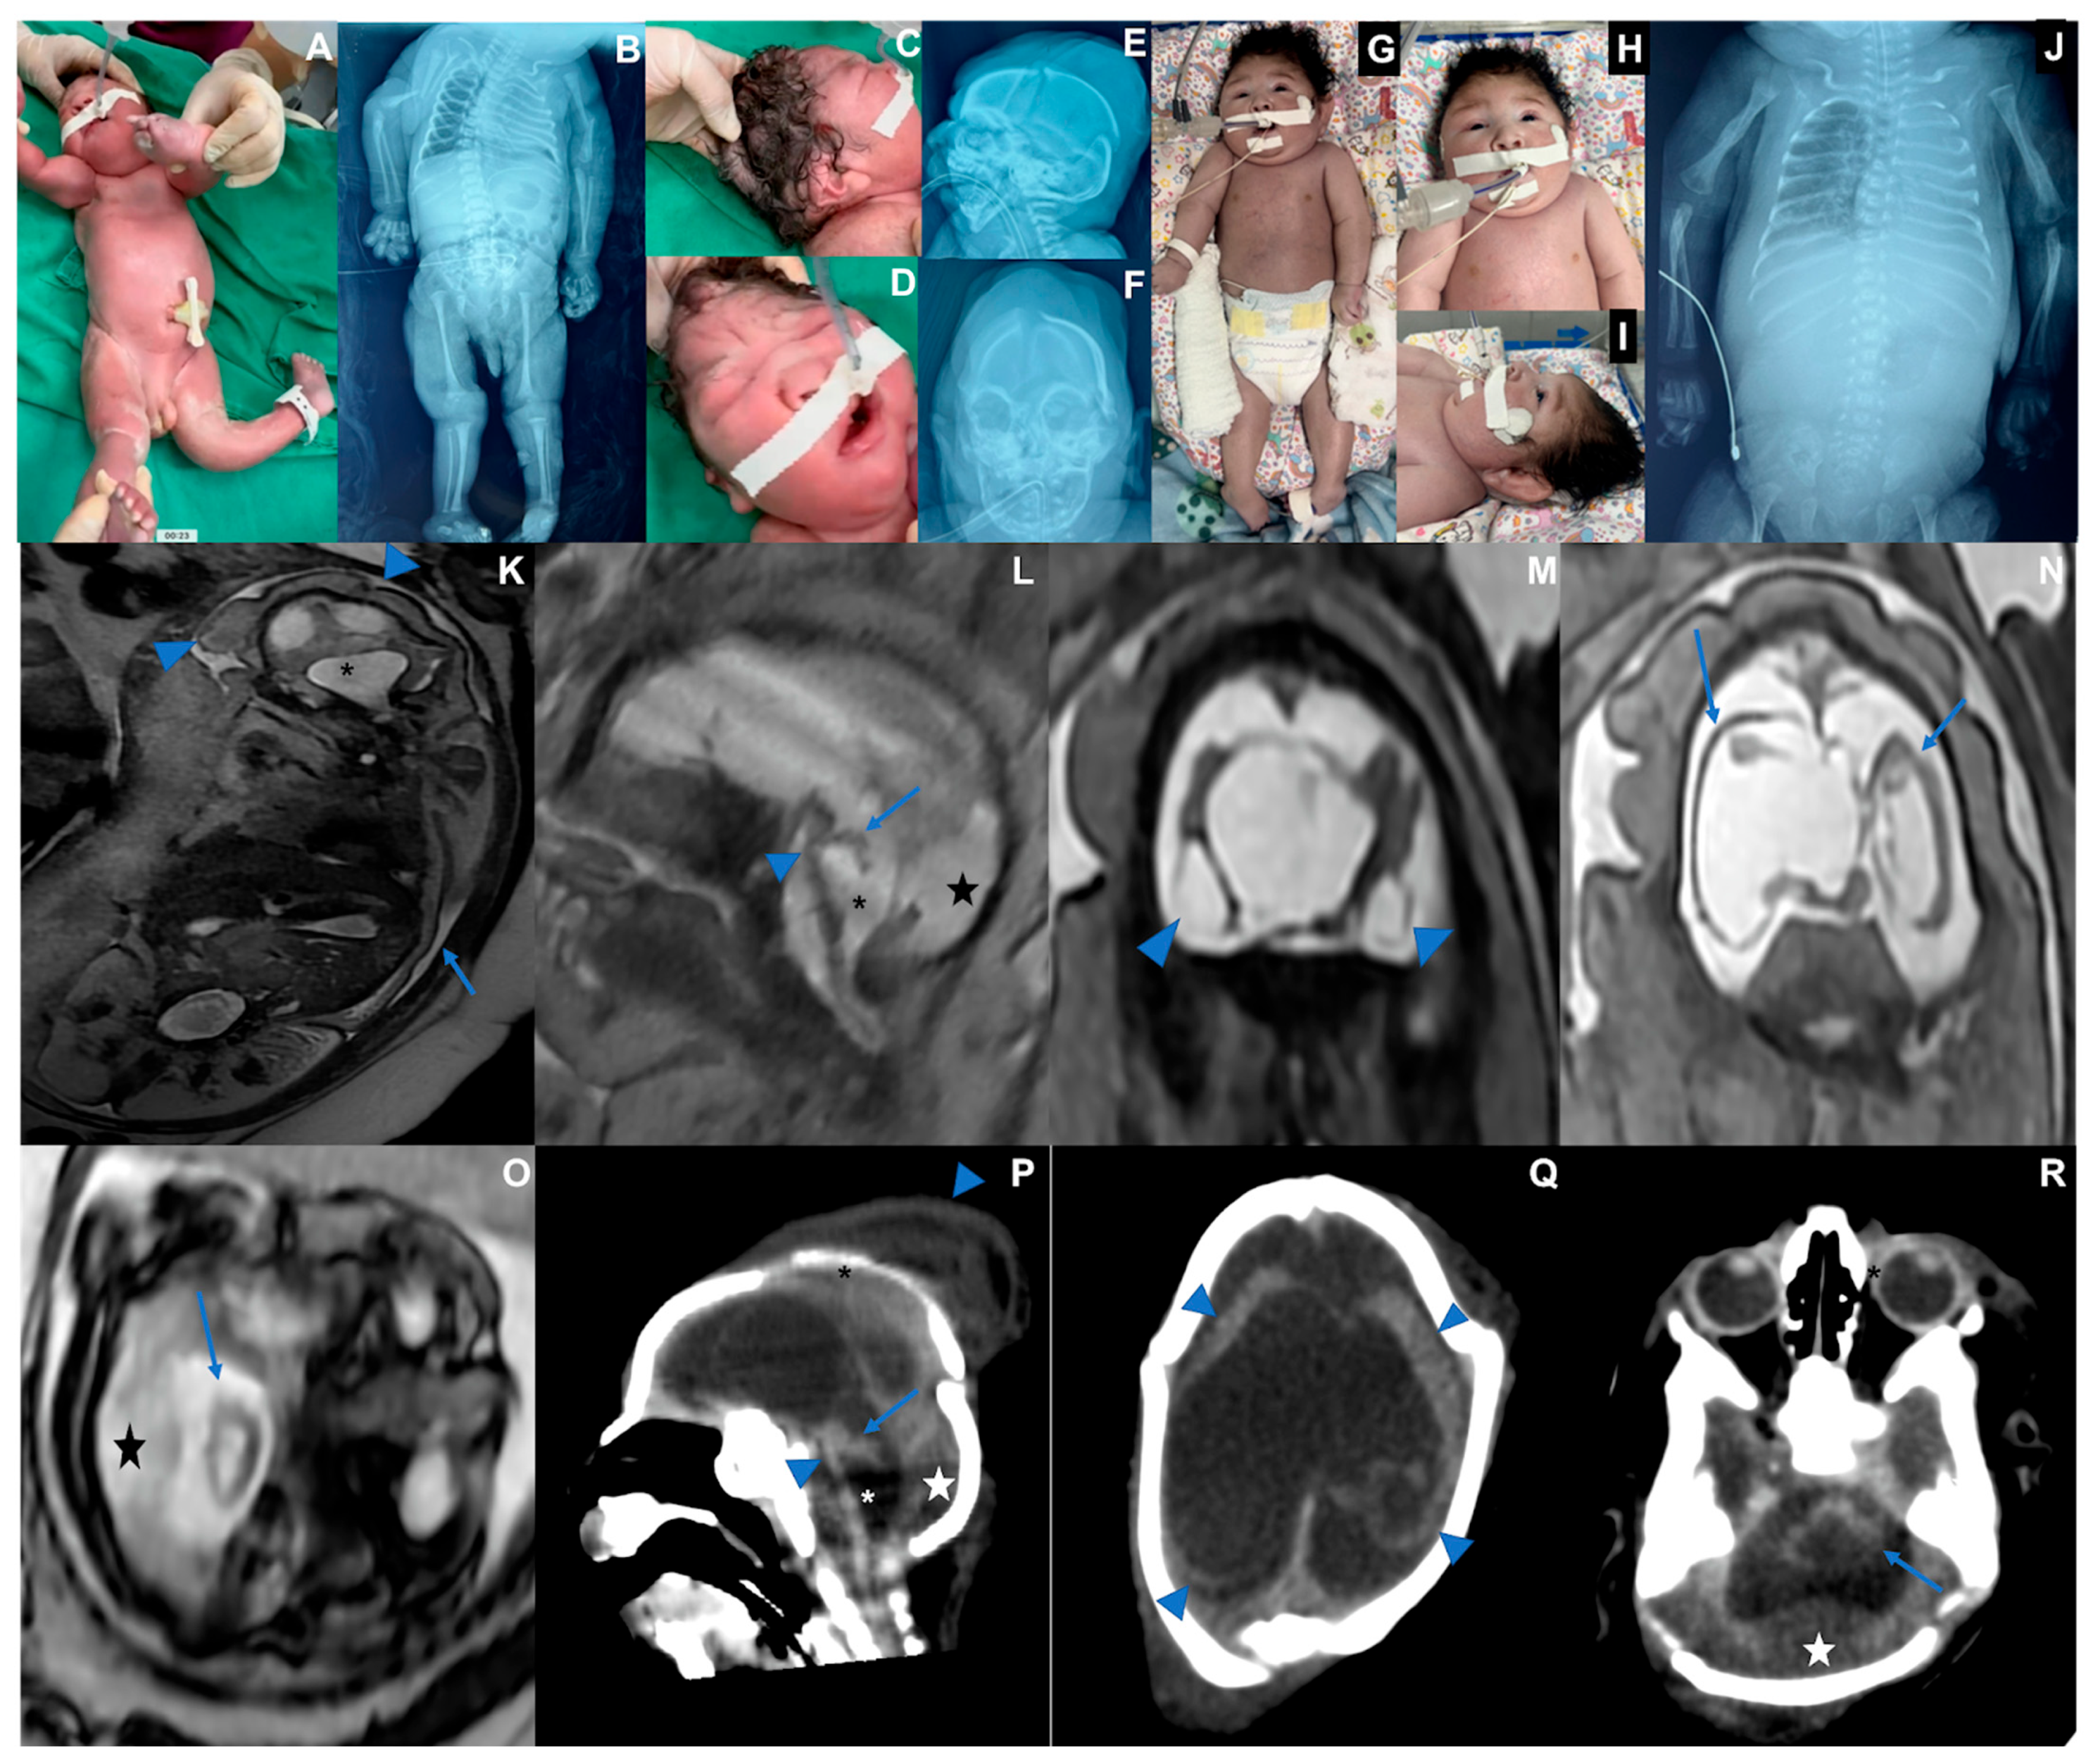

3.1. Case 1 (Figure 1)

| Microcephaly/Craniofacial disproportion/Skull collapse/short neck | Yes | Yes | Yes |

| Arthrogryposis multiplex | No | Yes | Yes |

| Fetal hydrops | No | Yes | Yes |

| Neurologic findings | Hypotonia, deep tendon hyperreflexia, dystonia, and epileptic seizures | Severe hypotonia (flaccid paralysis), no primitive or deep tendon reflexes, lack of suction, slow swallowing | Hypotonia, no deep tendon reflexes, lack of suction, slow swallowing |

| Ophthalmological findings | Visual impairment and nystagmus at 3 months | Corneal edema, optic disc atrophy, and chorioretinal scar in OU | Optic disc pallor and increased disc cupping (OS), chorioretinal macular scar and focal pigment mottling (OU), and vascular attenuation (OS) |

| Brain and Spinal Cord Images | Overlapping sutures, marked cerebral atrophy, partial lissencephaly, absent corpus callosum, brain cysts (cystic encephalomalacia and/or chronic subpial hemorrhages), subdural effusion, suspected striatal fusion, normal posterior fossa, normal spinal cord | Overlapping sutures, marked cerebral atrophy, absent corpus callosum, diffuse lissencephaly, severe brainstem and cerebellar hypoplasia, brain cysts (cystic encephalomalacia and/or chronic subpial hemorrhages), subdural effusion | Overlapping sutures, moderate cerebral atrophy, hypoplastic corpus callosum, diffuse lissencephaly, severe brainstem and cerebellar hypoplasia with Dandy–Walker-like features, intraventricular hemorrhage Global thinning of the spinal cord, mainly on the thoracic segment |